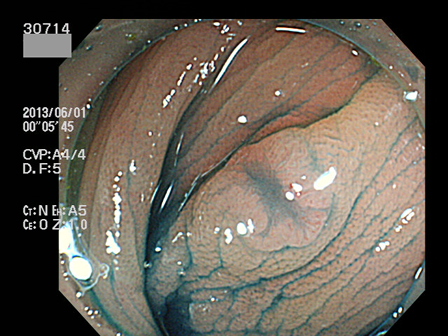

上記100名より抽出した平坦・陥凹型腺腫(=癌化の危険が高いが見落としやすい病変)の内視鏡写真